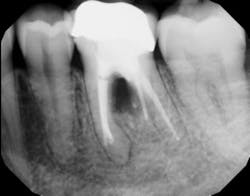

In other words, even experienced clinicians who access a root surface with flap surgery are sometimes limited in the amount of detoxification that can occur due to the depth of the defect and conventional instrumentation. (11) Further limitations with mechanical access to defects can come in the form of furcations with multirooted teeth. The diameter of the entrance to root furcation is usually smaller than the average tip of a curette, which can make access difficult (figures 1 and 1a). Molars with bone loss that includes furcations are often downgraded in prognosis due to this access difficulty. (12)

Figure 1: Molar with periodontal abscess due to furcation involvement

Figure 1a: Deep Class II furcation with an entrance smaller than the diameter of a curette tip